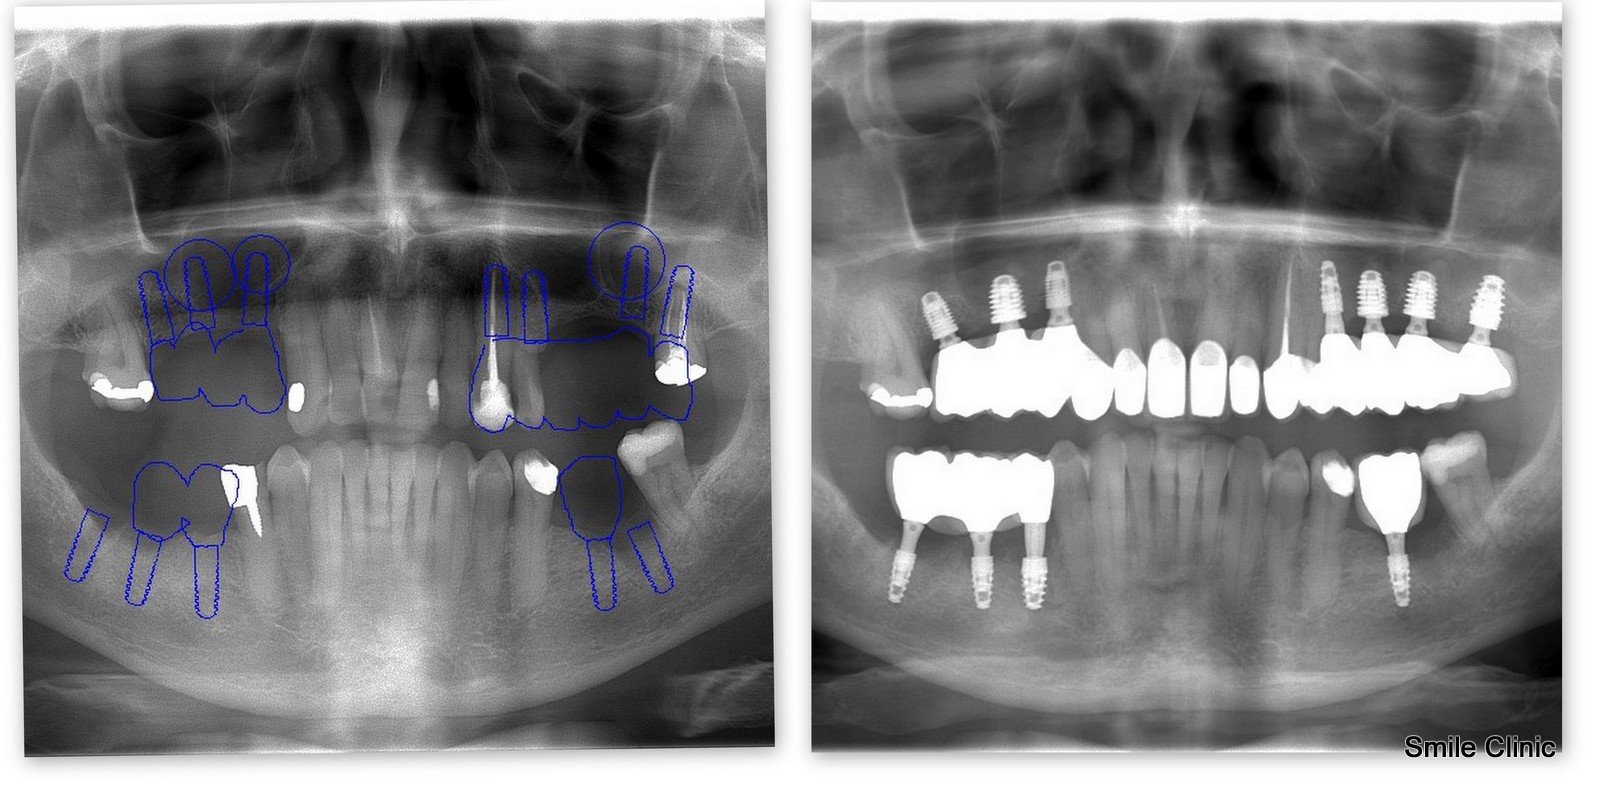

We placed 7 implants and crowns to the top jaw and 4 implants and crowns to the bottom jaw, saving some of his existing teeth.

Have a look here at the photographs, x-ray and hand-written testimonial to see the final result.